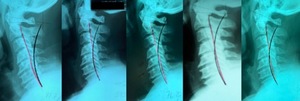

Alf Breig pioneered the biomechanics of the central nervous system.4–6 He showed, using cadaveric specimens, that flexion of the cervical spine unfolded the cord and could traction the brainstem to the level below the tentorium and that cervical extension relaxes the cord tension, also relaxing the tension in the lower brain structures. In patients with TN, Breig noted that most could elicit facial pain on head flexion and stated “there are other, hitherto overlooked, mechanisms for the precipitation of trigeminal neuralgia, amongst them the elongation the spinal canal and stretching of the pons-cord tract accompanying flexion of the cervical spine or the whole column.”5

Breig was a neurosurgeon and recommended cervicolordodesis (CLD) to place the cervical spine in an extended position to relax the spinal cord and related neural tissues in the treatment of various neurological disorders including TN. Strong evidence suggests that extension traction methods as developed by Chiropractic Biophysics® (CBP®) technique methods may restore the lordotic cervical alignment in craniocervical patients presenting with cervical hypolordosis/kyphosis,7–15 and it also aids in improving neurological symptoms.8,10,13

A full-spine radiographic assessment (Figures 2 and 3) was taken and analyzed using the Harrison posterior tangent method18,19 for the sagittal images and the modified Risser-Ferguson method19 for the coronal images. These methods are reliable and repeatable, as is posture.18–20 The images revealed a complete lack of cervical lordosis (absolute rotation angle from C2-C7=-1°; normal =34-42,21–23 forward head posture (FHP=35mm vs. <15mm normal22), and an atlas plane line (APL) of 10° (vs. 24-29 normal21,22) (Figure 3). The patient had well-demarcated osteoarthritic bone spurs from C4-C7 (Figure 3). On the posterior-anterior cervical radiograph, the patient had a left head translation of 7mm (vs. 0mm normal) (Figure 2).

As mentioned, Breig4–6 illustrated in several books definitive causes of neurological impingements based on spinal positions, including cervical flexion as eliciting symptoms in patients with trigeminal neuralgia.5 This is because any flexion of the spine lengthens the spinal canal and leads to an unfolding the cord and nerve roots.4,5 Once a spinal position surpasses some threshold, normal physiological cord unfolding changes to abnormal pathological cord tension. This is where a patient’s poor (forward flexed) posture may lead to neurologic symptoms.